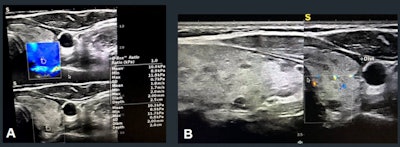

Specialists use TI-RADS to classify risk of malignancy based on ultrasound findings. But Aghaghazvini said that this does take a nodule's vascular or elastic characteristics into account. To address this knowledge gap, the team explored the value of adding vascularity and shear-wave elastography assessments to conventional TI-RADS assessments.

The study included 200 total thyroid nodules, assessed by conventional sonography to gather TI-RADS scores and important characteristics. The investigators used a 7.5 MHz probe to assess vascularity pattern and resistive index, performed quantitative elastography evaluations via color mapping, and calculated average and maximum velocities. They confirmed final diagnoses of all thyroid nodules via histopathology assessment or follow-up imaging.

Overall, area under the curve (AUC) for TI-RADS assessment was 0.76. Adding elastography and resistive index measures to the mix translated to higher AUC values for TI-RADS 4 and 5 nodules.